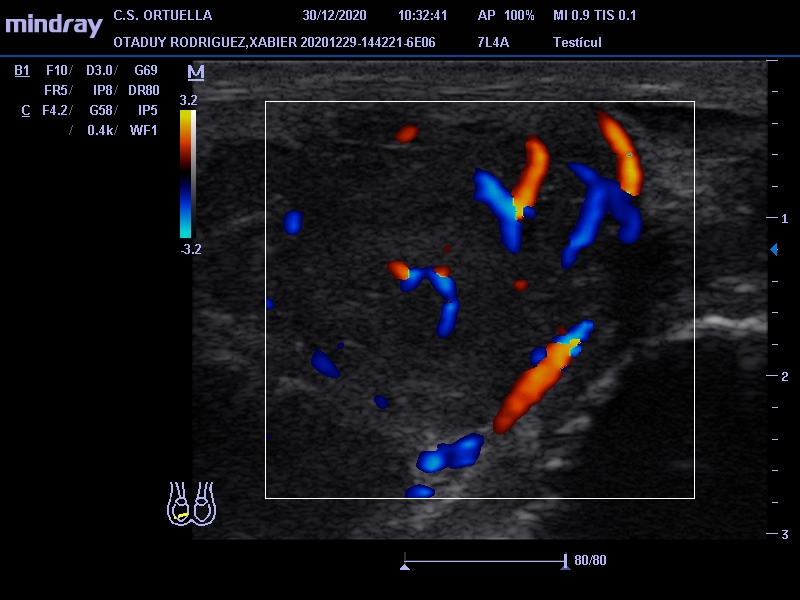

Hallazgos ecográficos

Masa de 38 x 40 mm, hipoecogénica, con aumento de vascularización mediante doppler, en polo inferior de teste derecho.